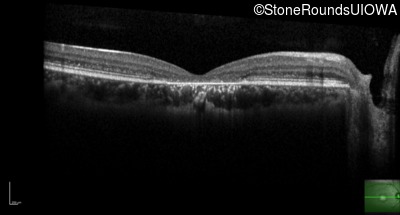

Age at visit: 19 years

Age at visit: 20 years

Age at visit: 21 years

The clinical features favoring the diagnosis of ABCA4-associated autosomal recessive Stargardt disease include: loss of acuity in the second decade, reduction in color discrimination and foveal photoreceptor loss on OCT.